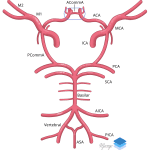

- Lobulated anterior communicating artery aneurysm involving both A1 and A2 segments

- ACA aneurysm

Lobulated anterior communicating artery aneurysm involving both A1 and A2 segments measuring 5 x 8 mm.